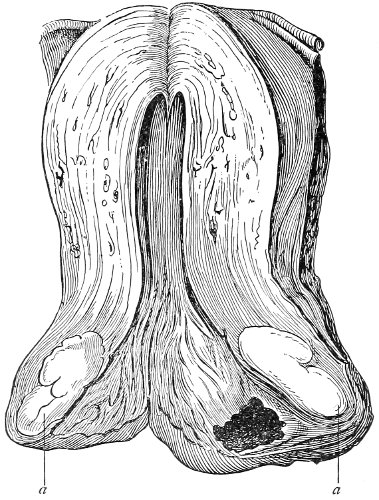

An accurate knowledge of the anatomy and mechanism of the female perineum is essential to an understanding of the nature and treatment of injuries to this structure. The anatomical structures lying between the anus behind and the symphysis pubis in front are those that most directly interest the gynecologist. Proceeding from 57 below upward, we find the following structures lying in superimposed planes: the skin, the superficial fascia, the deep layer of the superficial fascia, the transversus perinæi and the sphincter vaginæ muscles, the anterior layer of the triangular ligament, the posterior layer of the triangular ligament, the levator ani muscle (Fig. 19).

Fig. 18, A.—Superficial structures of the female perineum (Weisse).

Fig. 19.—Dissection of female perineum: on the left side the perineal muscles are exposed by the reflection of the perineal fascia; on the right side the muscles and the superficial layer of the triangular ligament have been removed, thereby exposing the deep layer of the ligament. S. V., Sphincter vaginæ muscle.

The vagina passes through these structures. They surround and support the ostium vaginæ as the fascia and muscles surround and support the opening of the rectum or the anus. The muscles and fasciæ are attached in the median line between the anus and the vagina, and therefore this part of the body, which is called the perineum, is supported or maintained in its 58 proper position by these various structures. The transversus perinæi arises from the ramus of the ischium and is inserted in the perineum. The bulbo-cavernosus, or sphincter vaginæ, arises in the perineum and is inserted in and about the clitoris. The inner fibers of the levator ani arise from the symphysis pubis and are inserted in the perineum and the lower part of the vagina (Fig. 20). When these muscles contract, their action, therefore, is to draw the perineum upward and forward. At the same time the anus is drawn upward and forward, and so also is the posterior margin of the ostium vaginæ and the lower portion of the posterior vaginal wall.

Fig. 20.—Dissection of female perineum, showing the deeper structures after removal of the levator and sphincter ani muscles.

The vagina has no circular sphincter like the anus, but 59 the vaginal month is kept closed by the action of the transversus perinæi, sphincter vaginæ, and levator ani muscles, which draw the perineum forward, and thus keep the posterior vaginal wall in apposition with the anterior wall.

Fig. 21.—Muscular floor of the pelvis seen from above.

This sling of muscles and fascia, which surrounds and supports the opening of the vagina, may readily be felt in the nulliparous woman by introducing the finger in the vagina and pressing backward and outward toward the ischio-rectal fossa. We then feel plainly, immediately within the ostium vaginæ, a firm resisting band of tissue, apparently about half an inch broad, embracing the posterior portion of the lower vagina. This band is formed by the inner edges of the various muscles and planes of fascia that have been described.

Fig. 22.—Sagittal section showing relations of the several layers of fascia within the pelvic floor (Dickinson).

The vagina extends, as a transverse slit in the pelvic floor, upward and backward, approximately in the direction 60 of a line drawn from the ostium vaginæ to the fifth sacral vertebra. It is approximately parallel with the conjugate of the brim, so that when the woman is erect the long axis of the vagina is inclined at an angle of 60° to the horizon. The vagina is not a vertical open tube: it is a slit in the pelvic floor, in health always closed by the accurate apposition of the anterior and posterior walls (Fig. 21). The anterior vaginal wall is about 2½ inches long in a vertical mesial line. The posterior vaginal wall is about 3½ inches long. The vaginal walls are triangular in shape, being broader above than below. The shape of the normal vagina at the pelvic outlet is shown by Fig. 23. The section here shows the vaginal 61 slit of the shape of the letter H. The portions of the slit extending backward and somewhat outward are called the vaginal sulci or furrows. They are directions of diminished resistance in which tears are liable to occur.

Fig. 23.—Section illustrating the characteristic form of the vaginal cleft (Henle): Ua, urethra; Va, vagina; L, levator ani; R, rectum.] 62